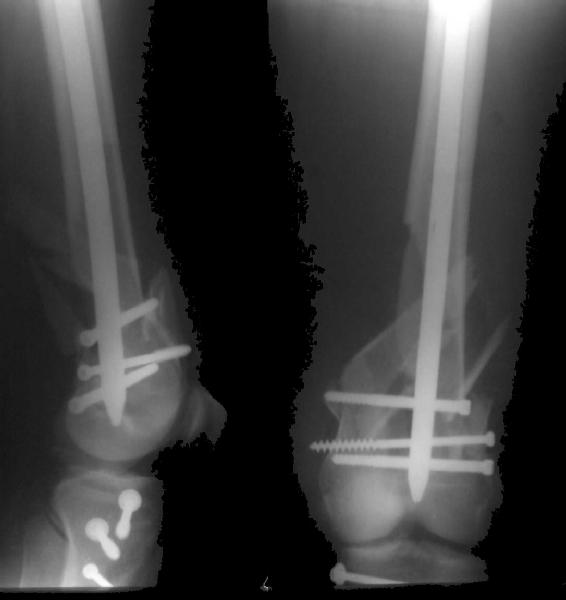

Look what we would have done.